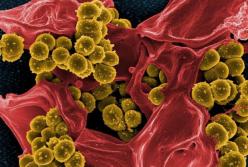

Почему мужчины чаще умирают от коронавируса: ученые назвали причину

Почему мужчины чаще умирают от коронавируса: ученые назвали причину

Ученые выяснили, почему от коронавируса чаще умирают мужчины, а не женщины. Дело в том, что у мужского пола более высокая концентрация ангиотензин-превращающего фермента 2 (АПФ2) в крови.